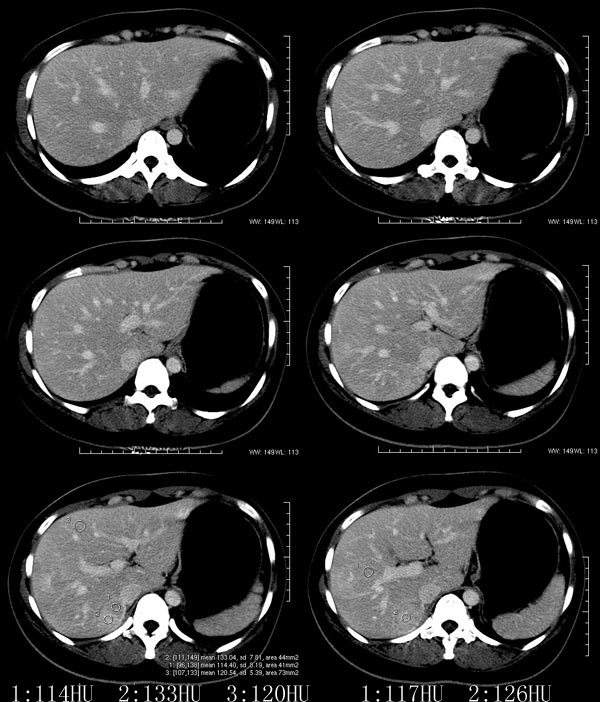

以下是引用52yingxiang在2007-9-16 10:16:00的发言:[br]肝脏局灶性结节增生影象表现(fnh)[br][br]肝脏局灶性结节增生是一种少见的肝脏良性肿瘤,可表现为边界清楚并无包膜的实质性肿块。病变大小不一,多系单发,亦可多发。组织学上是由结构紊乱的肝细胞、库普弗细胞、胆管、血管和粗厚的纤维性间隔所组成。[br]局灶性结节增生的ct表现可归纳为6点:[br]1、密度变化是其特征性改变,平扫多为低密度,少数为等密度,无论增强的早期或晚期均可能呈等密度,增强扫描有助于发现平扫为等密度的病灶;[br]2、中心疤痕,部分病灶在动态ct扫描时早期可看到中心疤痕增生性结节性病灶,ct血管造影也可看到普通ct不能显示的车轮状血管和车轴样改变;[br]3、纤维性分隔影,平扫为低密度,增强后为高密度;[br]4、包膜征象,增强后可以出现包膜强化,晚期较明显;[br]5、邻近血管的改变,主要是肝静脉受压,是发现等密度病变的重要依据;[br]6、瘤内胆管显影,这需要在胆管造影增强的情况下方能显示,出现率不高。[br][br]本例特点: 平扫低密度,增强动脉期明显强化,中心点条状低密度影(考虑纤维瘢痕),静脉期及延时期明显退减并与肝呈等密度,但中心仍可见低密度灶。[br]考虑肝脏局灶性结节增生(fnh)